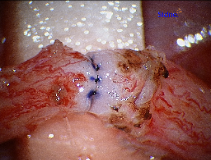

The initial step during a vasectomy reversal is to identify whether or not there are sperm in the testicular end of the vas deferens. If sperm are identified, then a vasovasostomy can be performed successfully using microsurgical technique. If sperm are not identified then a secondary epididymal obstruction has developed and re-connecting the vas deferens at the site of vasectomy will universally be unsuccessful. This occurs 30% of the time and is dependent on several factors such as the time since your vasectomy and the site of your vasectomy. If sperm are not seen then an epididymovasostomy will be required in order to reverse the vasectomy. (see below)

The next step in a vasectomy reversal is to re-approximate the ends of the vas deferens in a tension-free manner. The 10-0 Nylon suture provides a water-tight closure for the sperm to travel through the vas deferens. If larger sized suture is used, it can cause obstruction in the vasal lumen itself.